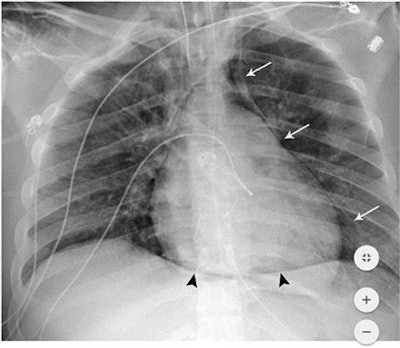

The NYU Langone researchers had observed a higher incidence of barotrauma in patients with COVID-19 and sought to determine if the disease was a risk factor for these events, which include pneumothorax, pneumomediastinum, pneumopericardium, and subcutaneous emphysema.

"Our observed high rate of barotrauma in patients with COVID-19 infection on [invasive mechanical ventilation] may support emerging theories of lung damage in SARS-CoV-2 infection," they wrote.